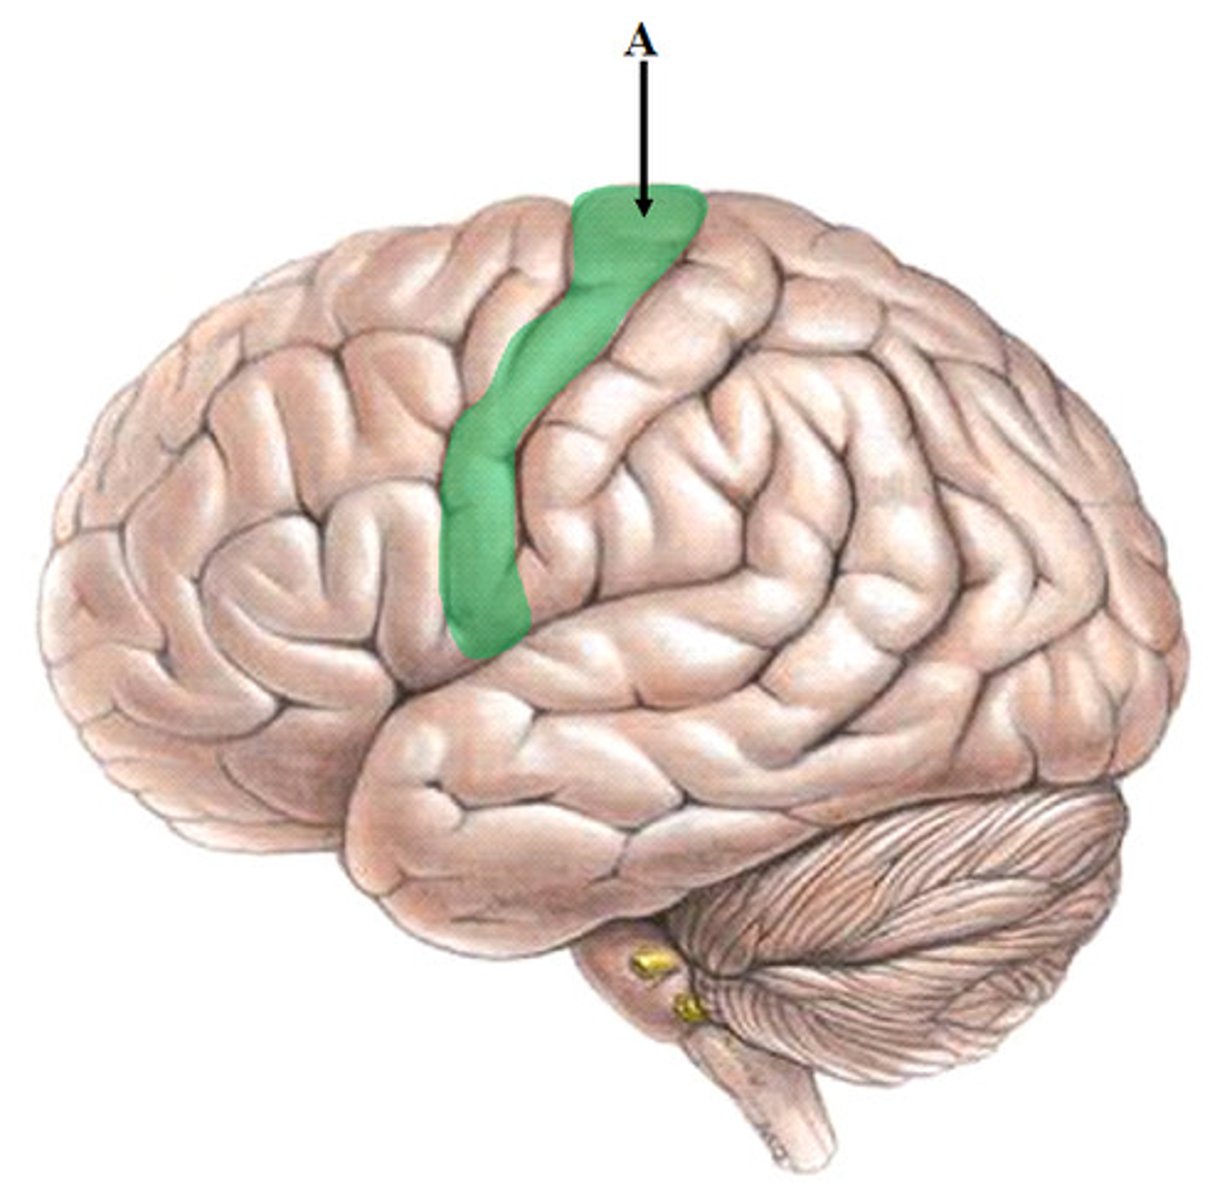

central sulcus

M1

primary motor cortex (precentral gyrus)

S1

primary somatosensory cortex